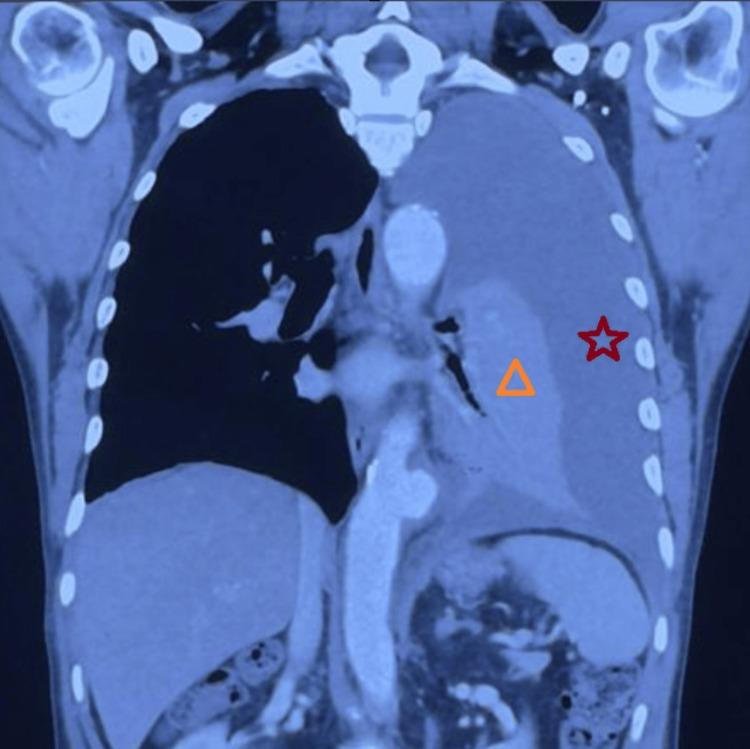

The rupture of a descending thoracic aortic aneurysm (DTAA) is a rare but critical vascular emergency that requires immediate recognition and action. It usually presents as a sharp, severe pain in the chest or back; however, some individuals exhibit non-typical symptoms resembling respiratory infections, leading to misdiagnosis and delays in definitive treatment. A 63-year-old male with a history of hypertension and smoking presented with left-sided chest pain to another hospital, where he was diagnosed with unstable angina based on clinical suspicion and managed conservatively with anti-anginal medication. Over the next three days, the patient developed a persistent cough, low-grade fever, and pleuritic pain, prompting referral to our hospital, where a lower respiratory tract infection (LRTI) was considered. On arrival, he was hemodynamically stable with a systolic BP of 100 mmHg and was managed with intravenous fluids, antibiotics, and nebulizers. Chest X-ray revealed moderate left pleural effusion with tracheal deviation, and thoracic ultrasound confirmed internal echoes suggestive of hemorrhagic content. Diagnostic thoracentesis yielded hemorrhagic fluid, prompting high-resolution computed tomography (HRCT), which showed a partially thrombosed 54 mm × 49 mm saccular aneurysm of the descending thoracic aorta with left lung collapse. Despite the rupture, the patient remained hemodynamically stable, suggestive of a contained event. A subsequent computed tomography angiogram (CTA) confirmed rupture into the pleural space and was the imaging modality that established the final diagnosis. The patient underwent thoracic endovascular aortic repair (TEVAR) using a 30 mm × 30 mm × 120 mm Ankura graft, selected for its conformability and effective sealing profile in emergencies. Postoperative recovery was uneventful. A CT aortogram on day three confirmed complete exclusion of the aneurysm with no endoleak, and a follow-up chest X-ray at two weeks showed full resolution of the hemothorax. This case illustrates the diagnostic challenge posed by atypical ruptured DTAA presentations and reinforces the importance of early CTA in unexplained pleural effusions, even in stable patients. Structured post-TEVAR surveillance remains critical to ensure long-term outcomes.

降主动脉瘤(DTAA)破裂是一种罕见但危急的血管急症,需要立即识别并采取行动。其通常表现为胸部或背部突发剧痛;然而,一些患者会出现类似呼吸道感染的非典型症状,导致误诊及确定性治疗延误。一名63岁男性,有高血压和吸烟史,因左侧胸痛前往另一家医院就诊,基于临床怀疑被诊断为不稳定型心绞痛,并接受抗心绞痛药物保守治疗。在接下来的三天里,患者出现持续咳嗽、低热和胸膜炎性疼痛,遂转诊至我院,当时考虑为下呼吸道感染(LRTI)。入院时,他血流动力学稳定,收缩压为100 mmHg,接受了静脉输液、抗生素和雾化治疗。胸部X线显示左侧中等量胸腔积液伴气管偏移,胸部超声证实内部回声提示为血性成分。诊断性胸腔穿刺抽出了血性液体,促使进行高分辨率计算机断层扫描(HRCT),结果显示降主动脉有一个54 mm×49 mm的部分血栓形成的囊状动脉瘤,伴左肺萎陷。尽管已经破裂,但患者血流动力学仍保持稳定,提示为局限性事件。随后的计算机断层血管造影(CTA)证实动脉瘤破裂进入胸腔,这一成像方式确立了最终诊断。患者接受了胸主动脉腔内修复术(TEVAR),使用了一枚30 mm×30 mm×120 mm的安珂拉移植物,选择该移植物是因其顺应性好且在紧急情况下具有有效的密封性能。术后恢复顺利。术后第三天的CT主动脉造影证实动脉瘤完全被隔绝,无内漏,术后两周的胸部X线随访显示血胸完全吸收。该病例说明了非典型破裂DTAA表现所带来的诊断挑战,并强调了早期CTA在不明原因胸腔积液中的重要性,即使是在病情稳定的患者中。TEVAR术后的结构化监测对于确保长期疗效仍然至关重要。